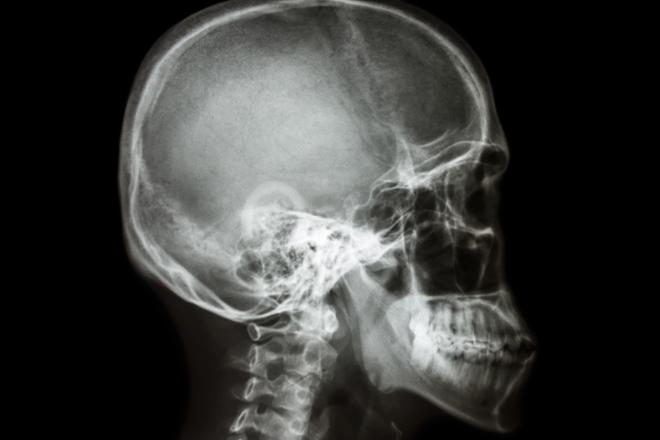

Una telerradiografía es una radiografía lateral de cráneo que se usa en los estudios de ortodoncia.